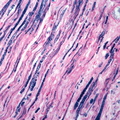

GROSS: NERVOUS: Brain: Carcinomatous Ventriculitis: Gross fixed tissue close-up of shaggy lateral ventricles oat cell carcinoma of lung primary